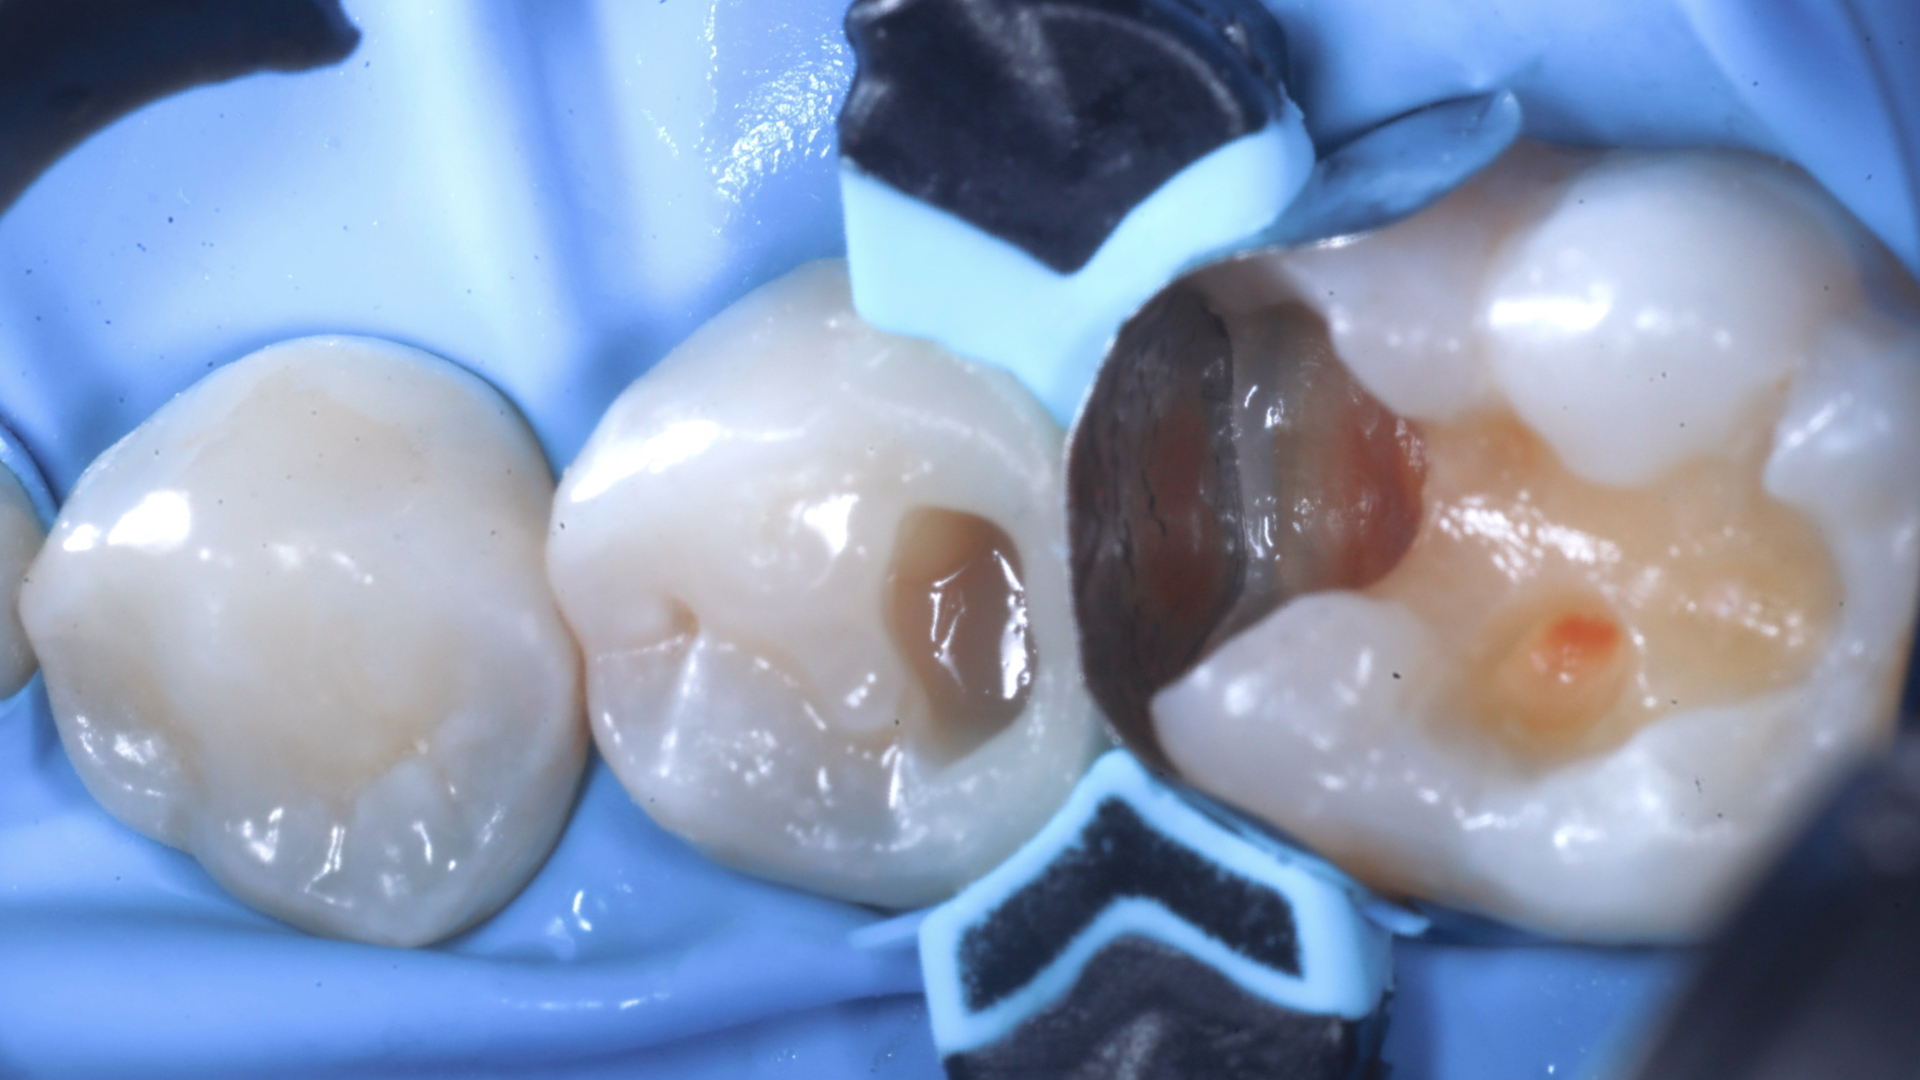

Radiografia bitewings iniziale che mostra un precedente restauro infiltrato mesiale a 2.6 ed un restauro debordante distale a 2.5Fotografia occlusale iniziale pre-opertoria

Isolamento con diga di gomma, creazione della cavità rimuovendo il vecchio restauro e la carie. Rifinitura della stessa cavità con frese diamantate a granulometria ridotta, strumenti reciprocanti e polveri a base di glicina Verifica fotografica del sigillo cervicale mesiale a 2.6